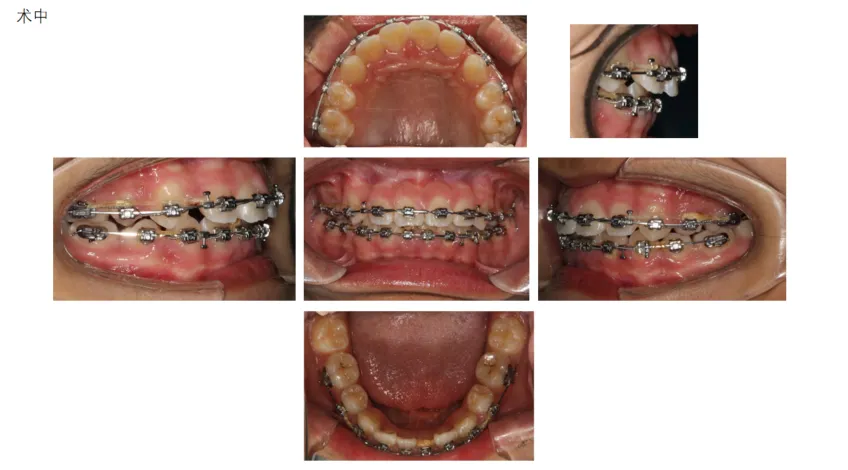

病例展示: